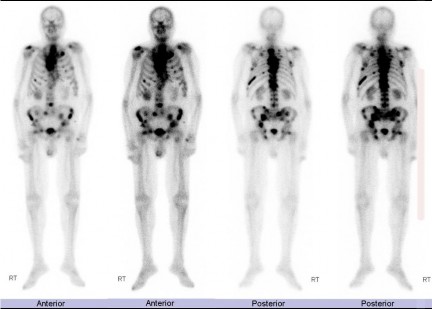

Xạ hình xương: Là phương pháp được sử dụng rộng rãi nhất để phát hiện di căn xương vì nó cung cấp hình ảnh của toàn bộ bộ xương. 99m- Tc-methylene diphosphonate ( 99m Tc-MDP) là chất đánh dấu được sử dụng phổ biến nhất. Nó tích tụ trong các khu vực tăng hoạt động của nguyên bào xương, giúp kiểm tra tổng thể bộ xương và đáng tin cậy để phát hiện di căn trong các bệnh như ung thư tuyến tiền liệt [46].

Hình 1. 5 Xạ hình hạt nhân phóng xạ technetium Tc-99m methylene diphosphonate cho thấy nhiều ổ hấp thu bất thường trong toàn bộ khung xương, ví dụ như xương bả vai 2 bên, nhiều xương sườn 2 bên, cột sống thắt lưng, xương chậu 2 bên và cổ xương đùi thứ phát [18]